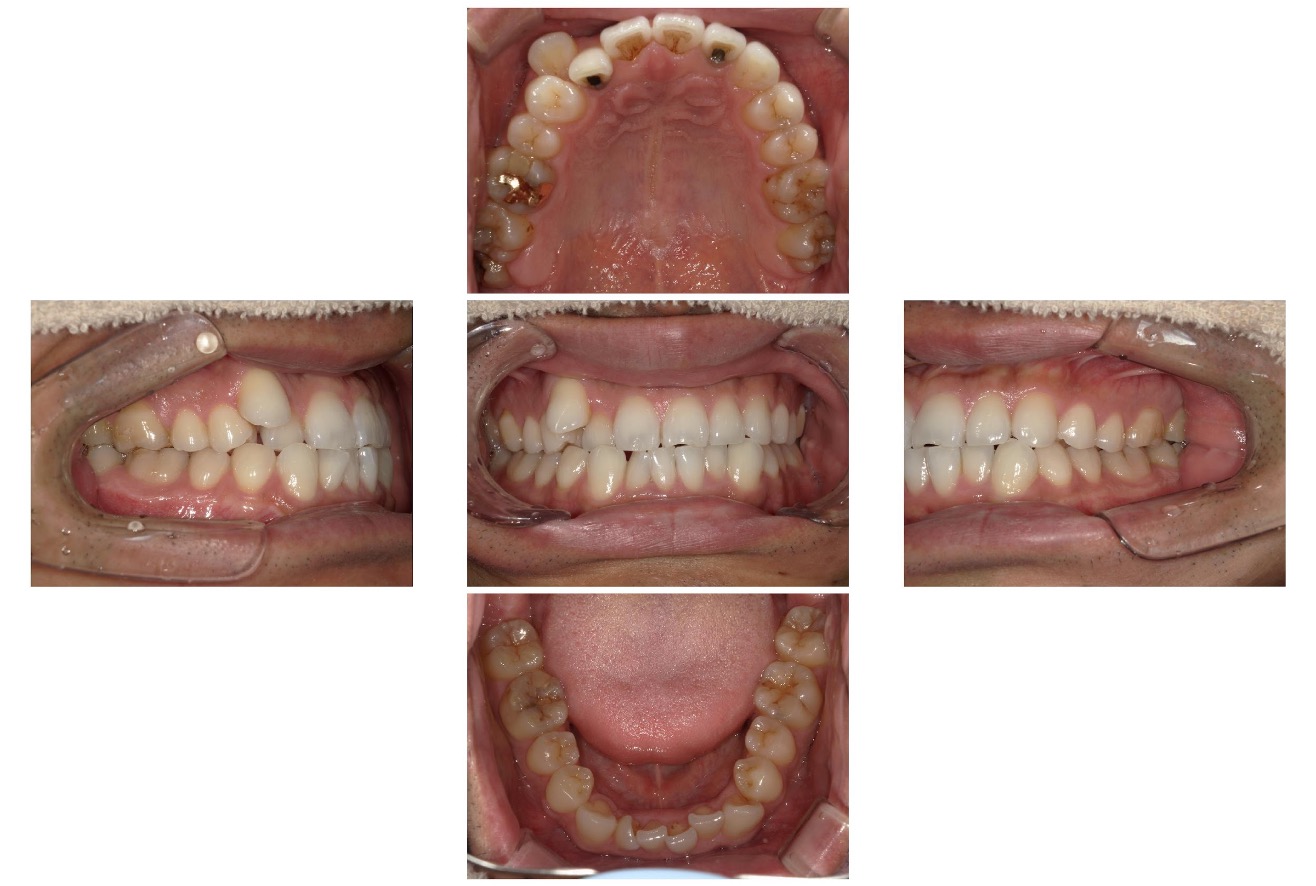

Case.06

治療前

治療後

| 主訴 | 八重歯と上下の凸凹を治したい |

|---|---|

| 治療 期間 | 2年6ヶ月 |

| 治療費 | 880,000円 (税込968,000円) |

| 治療 内容 | インビザライン 右上4 抜歯 顎間ゴム |

| 治療の リスク | 1日に20時間以上装着しないと、予定通りに歯が動かないことがあります。 装着後数日痛みがあります。 |